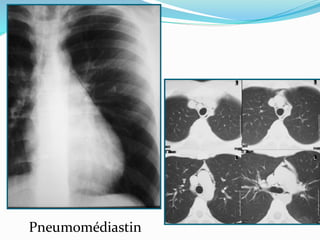

Pneumomédiastin

3e question : pneumomédiastin ?

 Signe du diaphragme continu.

 Hyperclarté péricardiaque.

 Collections aériques linéaires, au niveau des parties

molles du cou et de la paroi thoracique.

 Présence d`air autour de l`artère pulmonaire et de ses

branches.

 Collection aérique autour des troncs supra-aortiques.